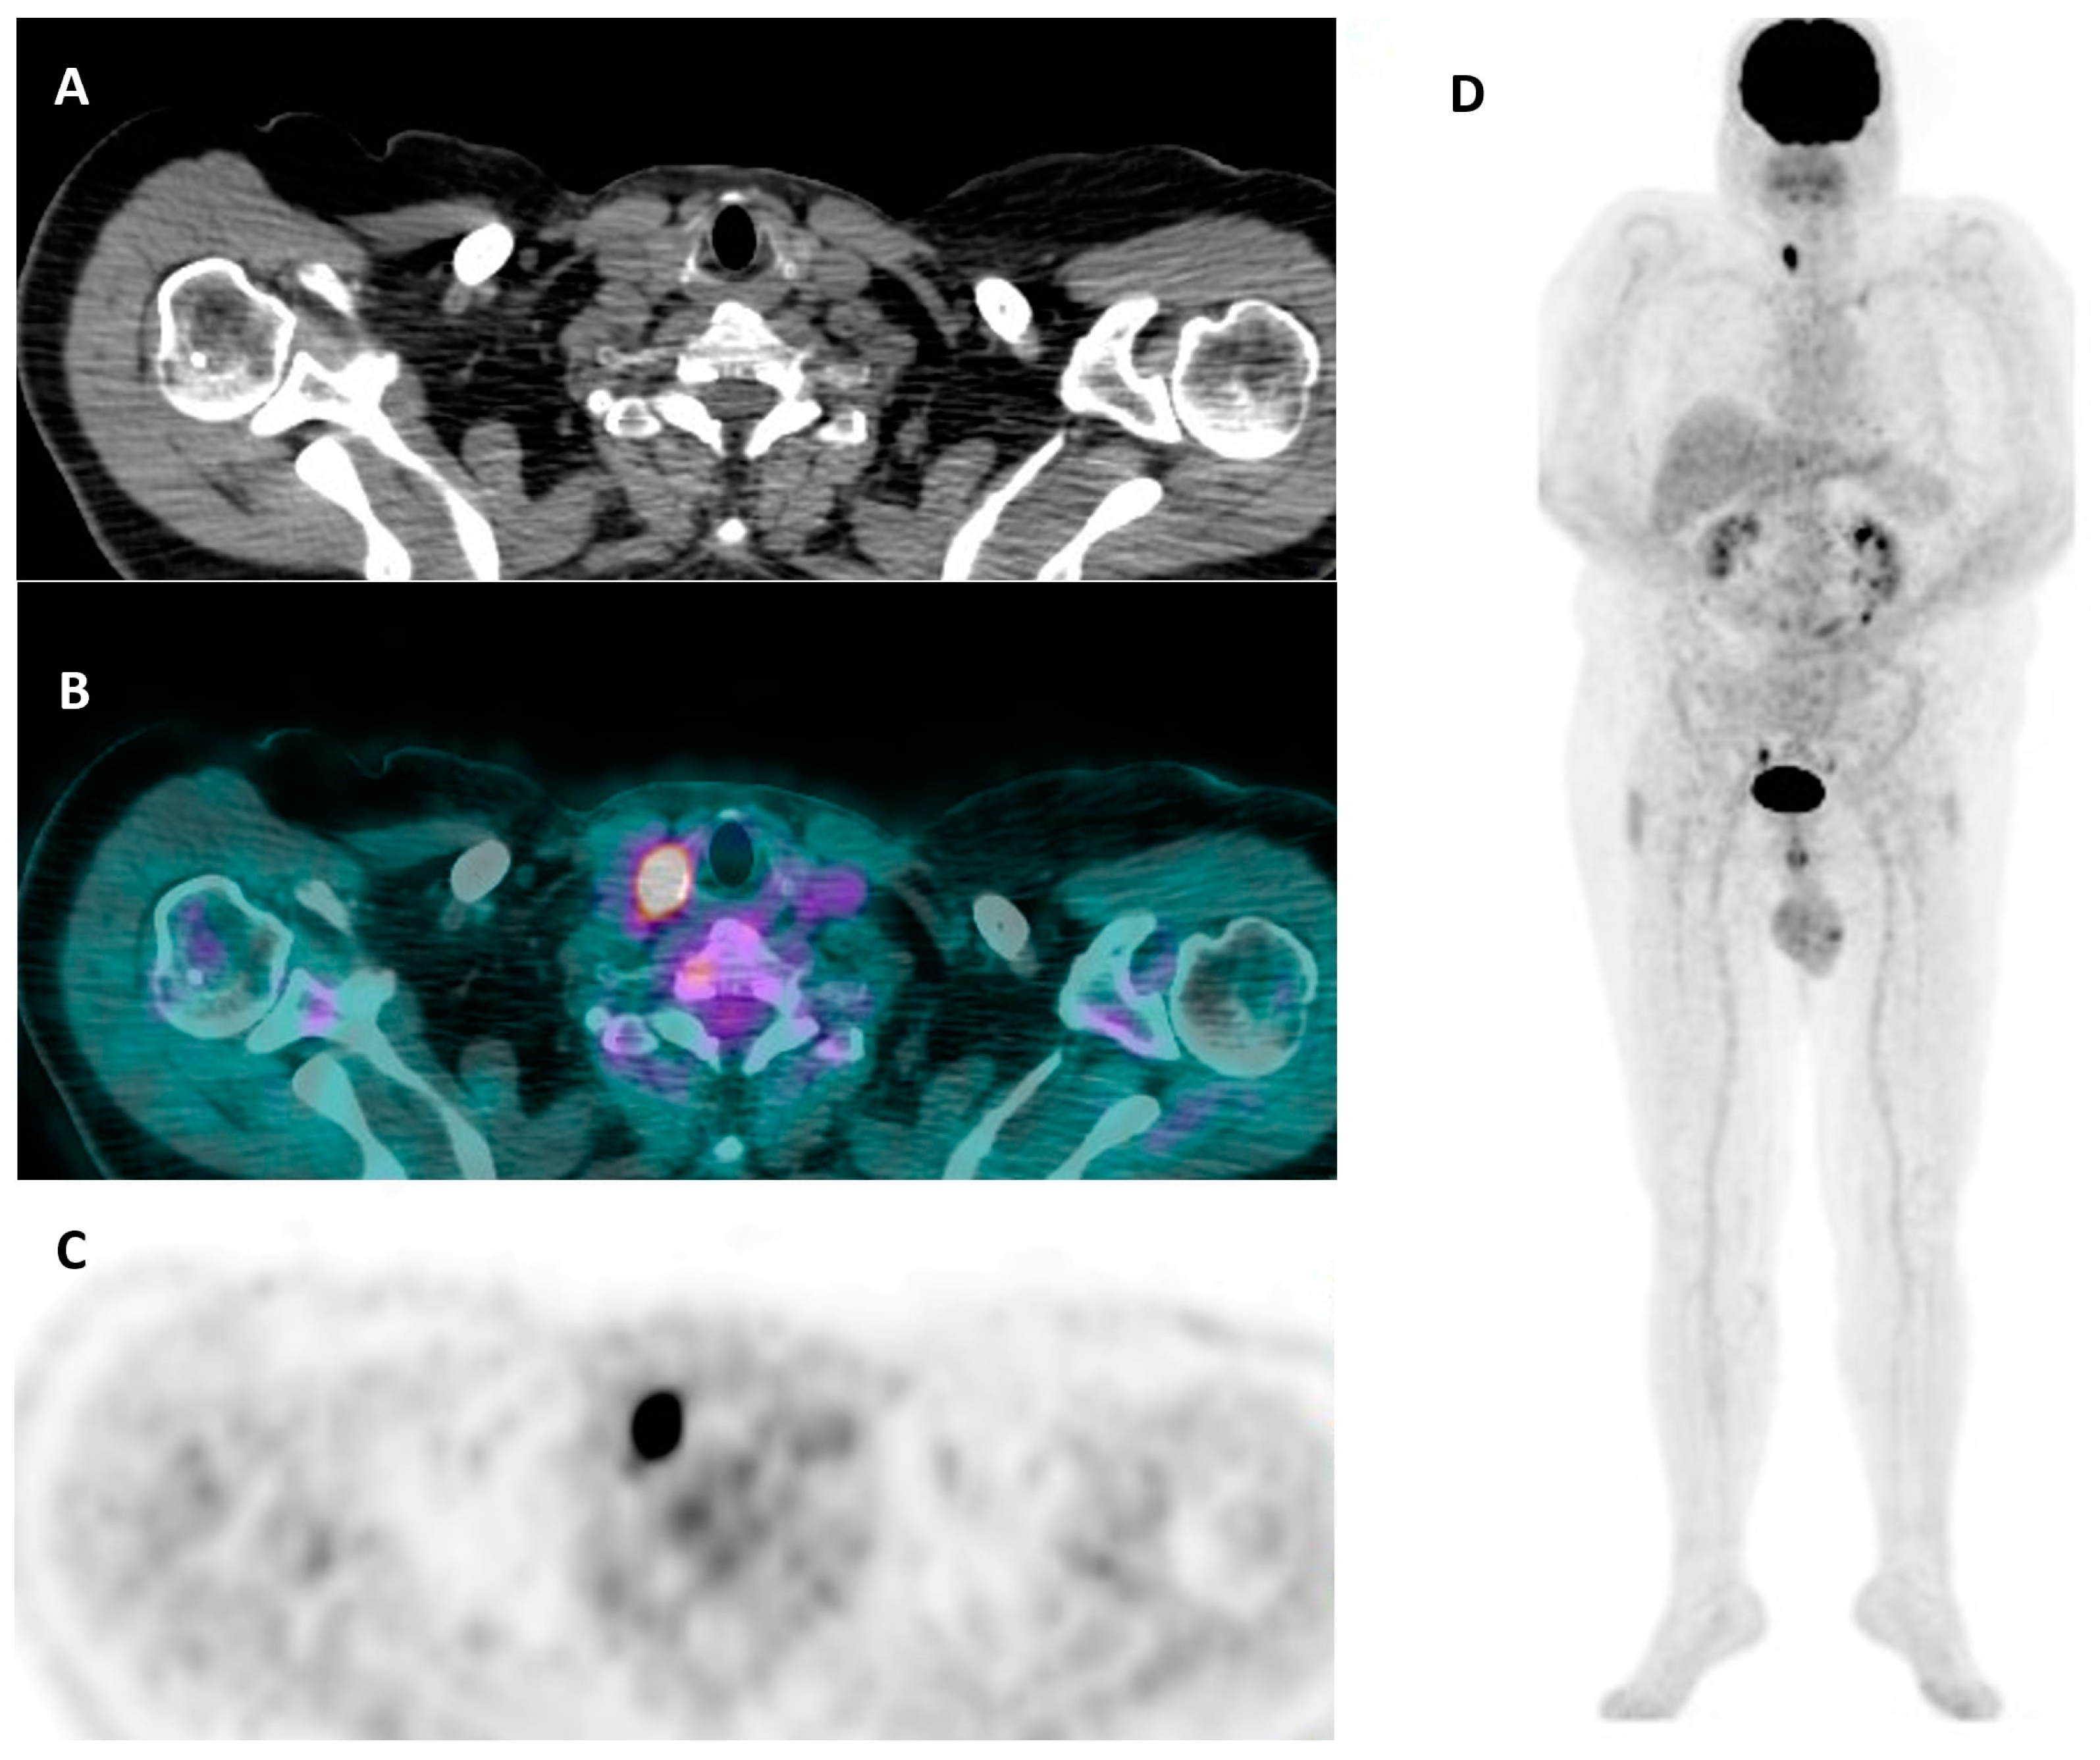

- de Koster, E.J.; de Geus-Oei, L.F.; Brouwers, A.H.; van Dam, E.W.C.M.; Dijkhorst-Oei, L.T.; van Engen-van Grunsven, A.C.H.; van den Hout, W.B.; Klooker, T.K.; Netea-Maier, R.T.; Snel, M.; et al. [18F]FDG-PET/CT to Prevent Futile Surgery in Indeterminate Thyroid Nodules: A Blinded, Randomised Controlled Multicentre Trial. Eur. J. Nucl. Med. Mol. Imaging 2022, 49, 1970–1984. [Google Scholar] [CrossRef]

- Vriens, D.; De Wilt, J.H.W.; Van Der Wilt, G.J.; Netea-Maier, R.T.; Oyen, W.J.G.; De Geus-Oei, L.F. The Role of [18F]-2-Fluoro-2-Deoxy-d-Glucose-Positron Emission Tomography in Thyroid Nodules with Indeterminate Fine-Needle Aspiration Biopsy: Systematic Review and Meta-Analysis of the Literature. Cancer 2011, 117, 4582–4594. [Google Scholar] [CrossRef]

- Wang, N.; Zhai, H.; Lu, Y. Is Fluorine-18 Fluorodeoxyglucose Positron Emission Tomography Useful for the Thyroid Nodules with Indeterminate Fine Needle Aspiration Biopsy? A Meta-Analysis of the Literature. J. Otolaryngol. Head Neck Surg. 2013, 42, 38. [Google Scholar] [CrossRef]

- Castellana, M.; Trimboli, P.; Piccardo, A.; Giovanella, L.; Treglia, G. Performance of 18 F-FDG PET/CT in Selecting Thyroid Nodules with Indeterminate Fine-Needle Aspiration Cytology for Surgery. A Systematic Review and a Meta-Analysis. J. Clin. Med. 2019, 8, 1333. [Google Scholar] [CrossRef] [PubMed]

- Giovanella, L.; Milan, L.; Piccardo, A.; Bottoni, G.; Cuzzocrea, M.; Paone, G.; Ceriani, L. Radiomics Analysis Improves 18FDG PET/CT-Based Risk Stratification of Cytologically Indeterminate Thyroid Nodules. Endocrine 2022, 75, 202–210. [Google Scholar] [CrossRef] [PubMed]

- de Koster, E.J.; Noortman, W.A.; Mostert, J.M.; Booij, J.; Brouwer, C.B.; de Keizer, B.; de Klerk, J.M.H.; Oyen, W.J.G.; van Velden, F.H.P.; de Geus-Oei, L.F.; et al. Quantitative Classification and Radiomics of [18F]FDG-PET/CT in Indeterminate Thyroid Nodules. Eur. J. Nucl. Med. Mol. Imaging 2022, 49, 2174–2188. [Google Scholar] [CrossRef] [PubMed]